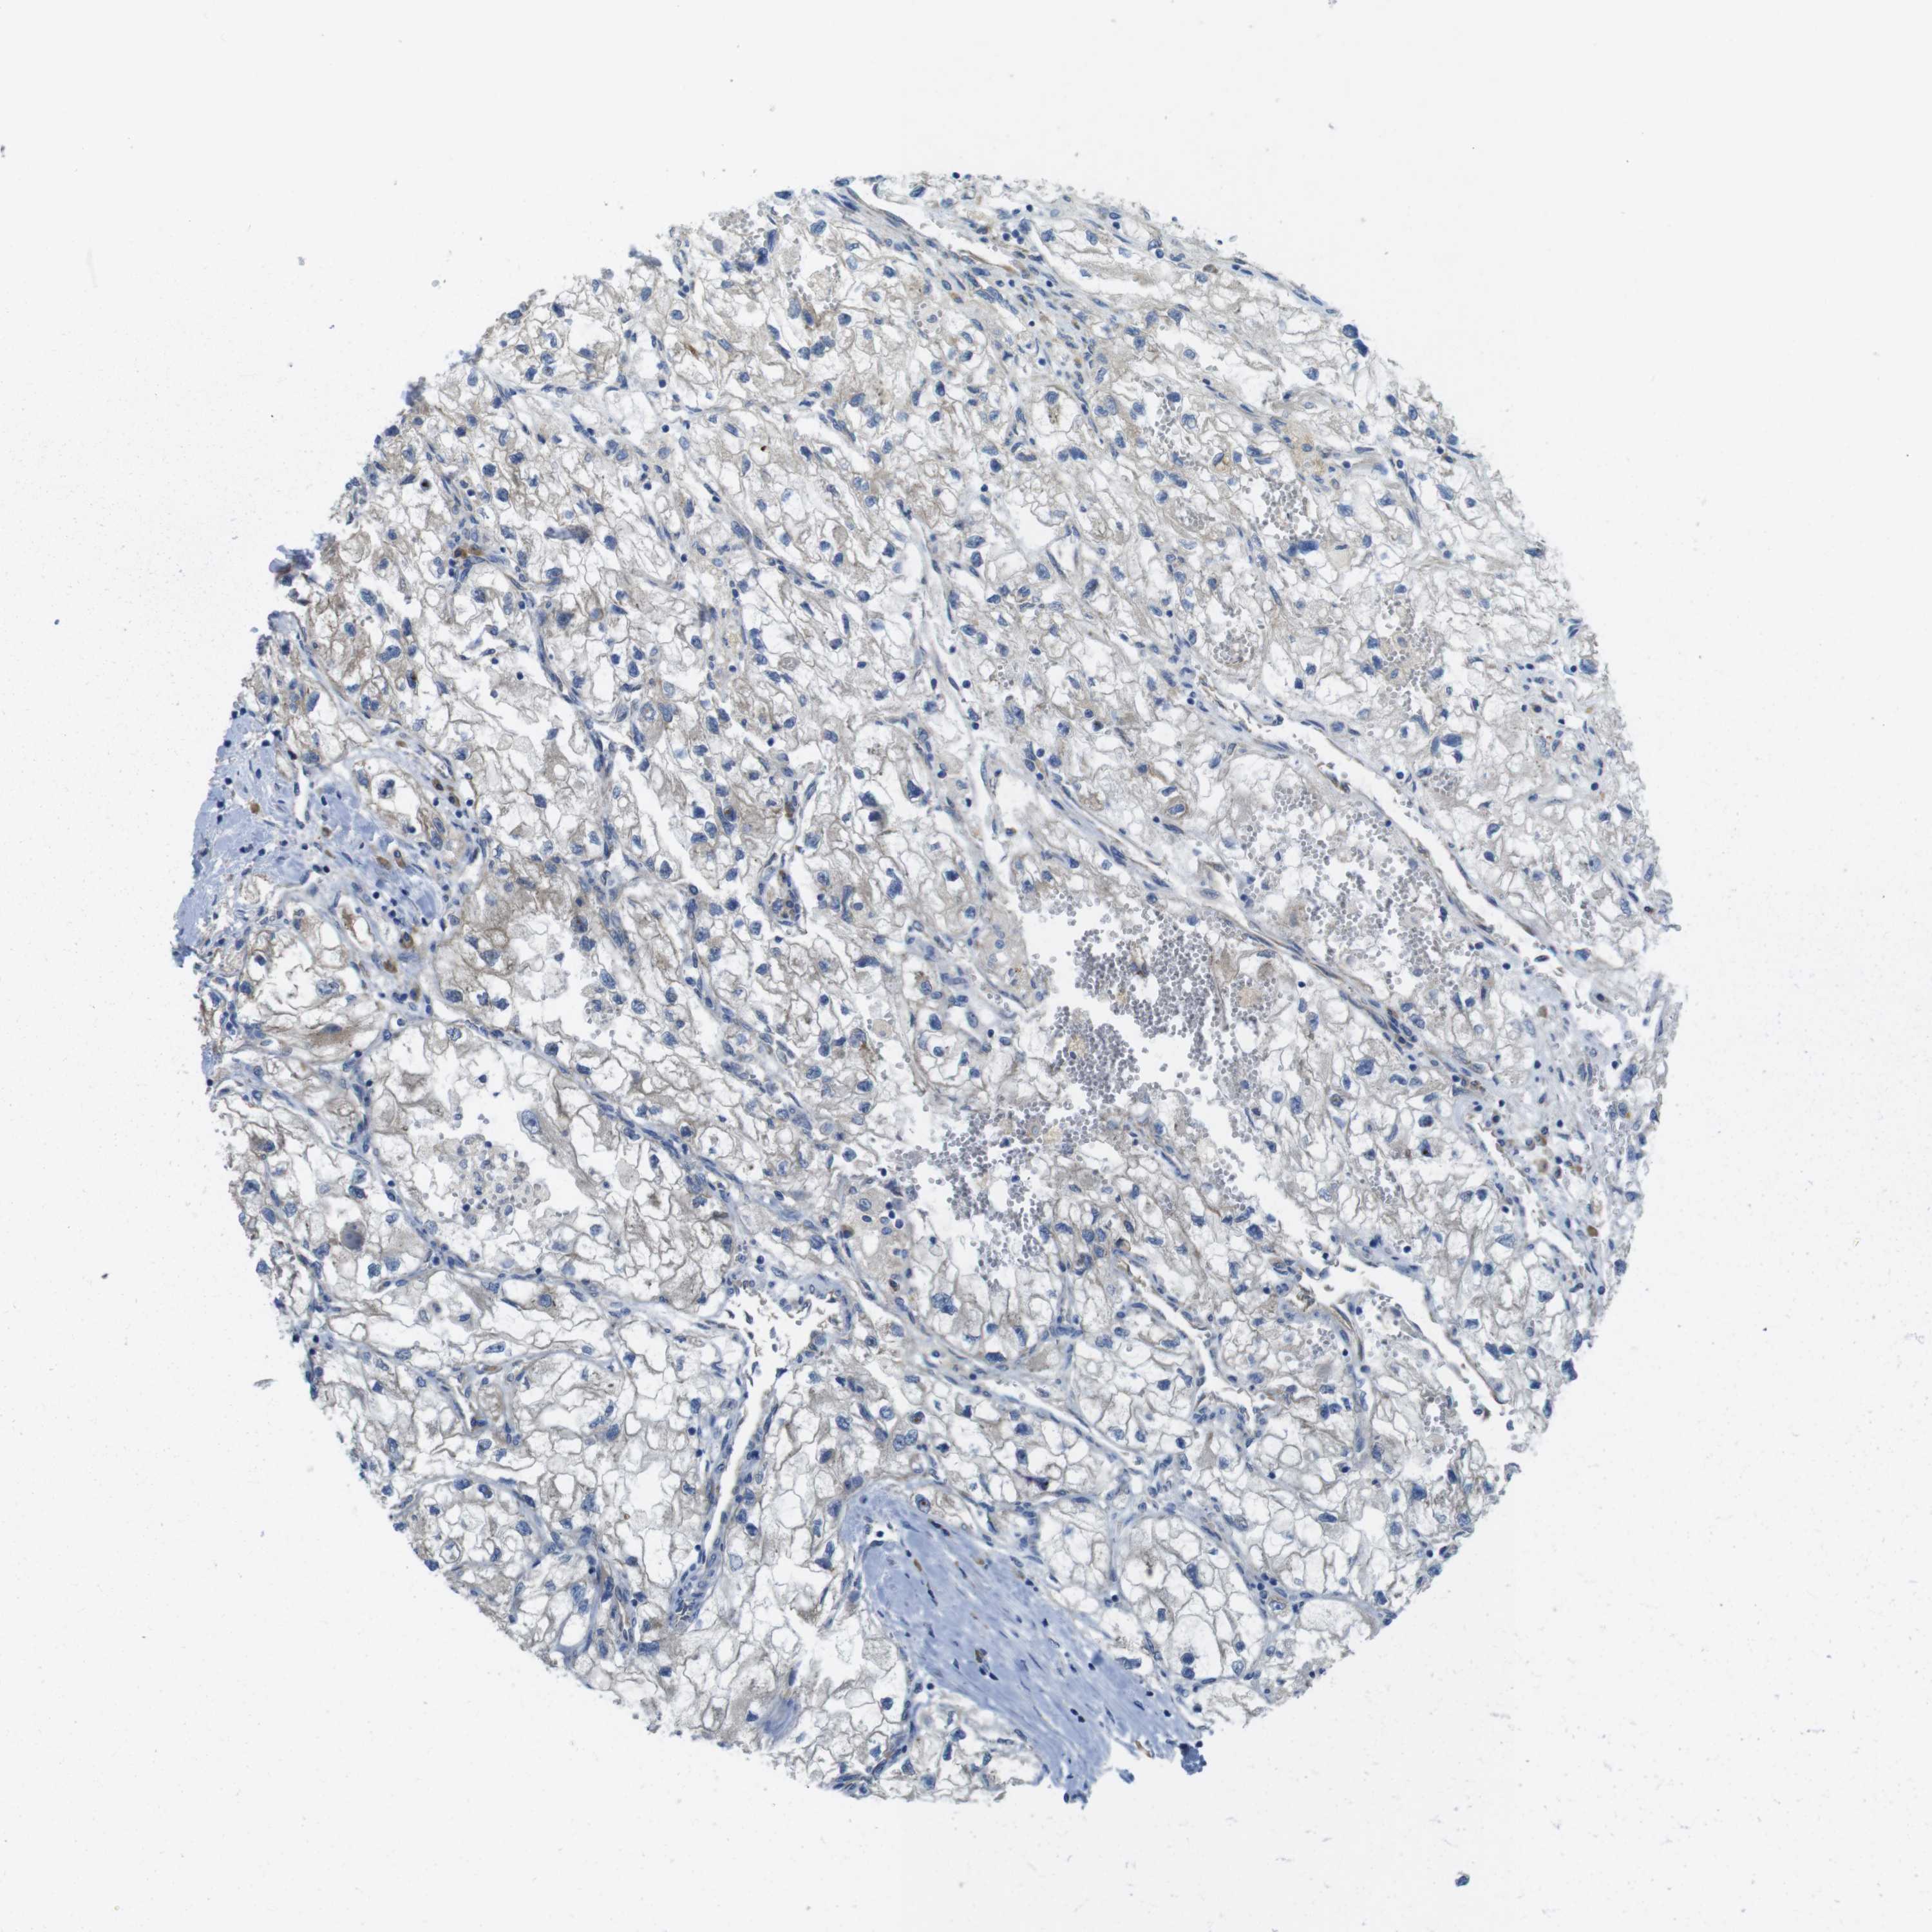

KICH TCGA KIRC TCGA KIRC VALIDATION KIRP TCGA PROTEIN RCC CPTAC PROTEIN EXPRESSION

Renal cancer

Kidney renal papillary cell carcinoma

KIDNEY RENAL PAPILLARY CELL CARCINOMA (TCGA) - Interactive survival scatter ploti

TMEM234 is not prognostic in Kidney Renal Papillary Cell Carcinoma (TCGA)

Best expression cut offi